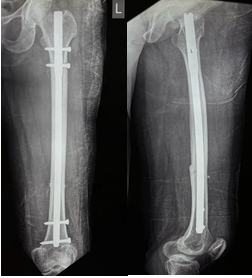

Figure 4: Anteroposterior and lateral views at 6 months showing distal third fracture of the femur with retrograde nail.

Out of all study participants, 58 patients had closed fractures and rest 2 patients had compound fractures. The mean operation-injury interval was 5.5 ± 0.67 days for antegrade nailing and 5.8 ± 0.65 days for retrograde nailing. The mean duration of the surgery was 85 ± 2.15 min for retrograde nailing and 95 ± 1.39 min for antegrade nailing. Mean time for radiological union with retrograde nailing was 10 ± 0.38 weeks (Fig. 1, 2, 3, 4) and with antegrade nailing, it was 14 0.44 weeks (Fig. 5, 6).

The mean post-operative knee ROM achieved with retrograde nailing was 117.3 ±2° and with antegrade nailing, it was 114.4 ± 1.8°. Mean time for partial weight bearing was 9.27 ± 0.37 weeks with retrograde nailing, an 10.9 ± 0.49 weeks in antegrade nailing. Mean time for full weight bearing was 15 ± 0.47 weeks in retrograde nailing and 18.2 ± 0.67 weeks in antegrade nailing (Tables 3, 4, 5).

As per Neers’ scoring system in the retrograde nailing group, 20 (67.7%) had excellent outcome, 7 (23.3%) had good outcome, and 3 (10%) had fair outcome. In antegrade nailing group, 8 (26.7%) had excellent outcomes, 15 (50%) had good outcome, and 7 (23.3%) had fair outcome.